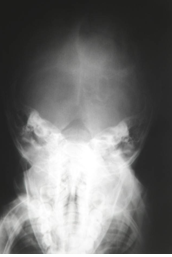

O que pode ser bem visualizado em uma Rx Bretton?

Região occipital, côndilo mandibular.

Forame magno e arco de C1 (aparece dentro do forame magno).